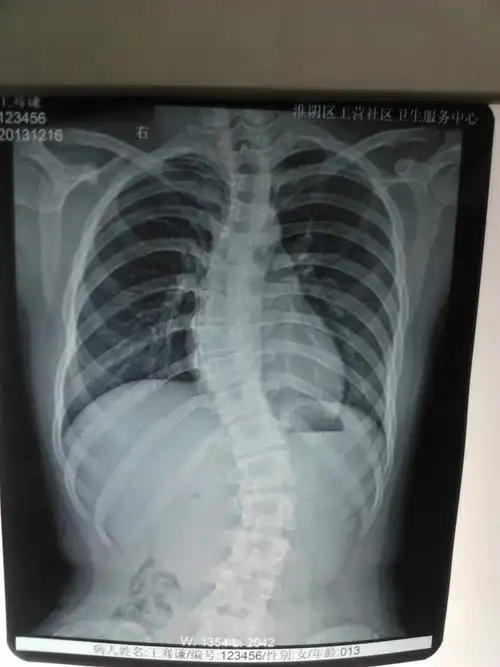

成年人轻度脊柱侧弯没关系事实你还得长点心

所患疾病:脊柱侧弯 病情描述:女孩,14岁,刚刚检查x片子发现脊柱s形状

40度脊柱侧弯是接受保守治疗还是做手术